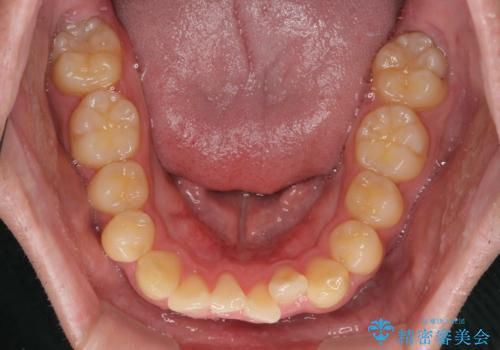

- 上下前歯の捻れやデコボコを気にして来院された患者様です。

マウスピース矯正でもワイヤー矯正でも対応可能でしたが、極力楽をして治したいとのことでワイヤー装置にて治療をおこなうこととしました。

口元はそれほど突出しておらず、患者様自身も気にしていらっしゃいませんでしたが、前歯の捻れやデコボコを解消すると、前方に拡大され、治療後に出っ歯仕上がりとなるリスクがあったため、補助装置により上顎臼歯を後方移動していくこととしました。